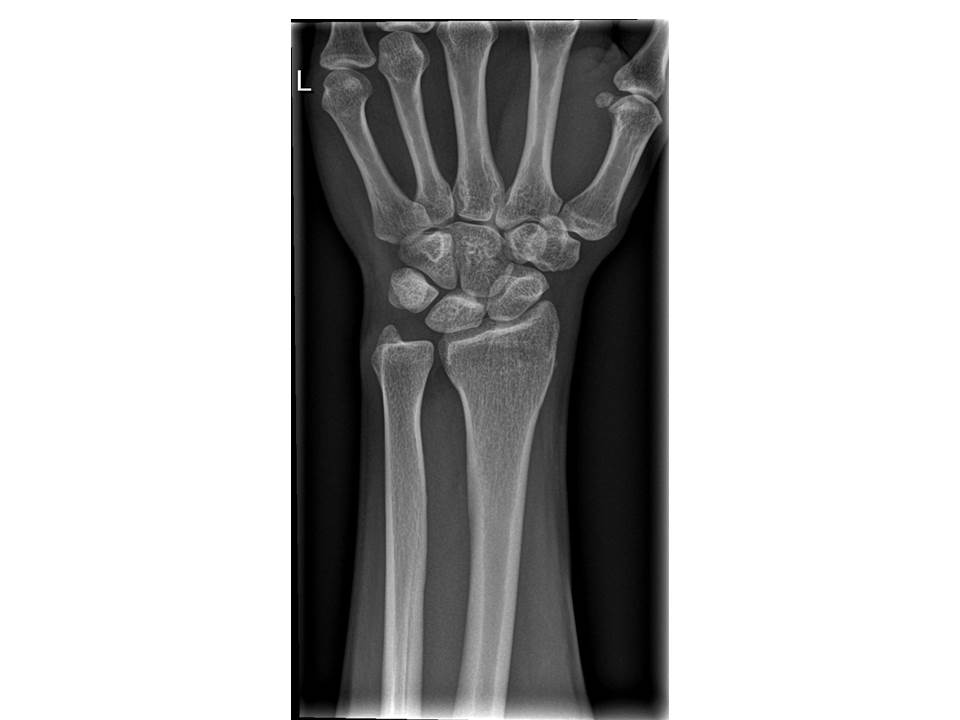

На фото  - рентгенограма дистального відділу верхньої кінцівки (пряма проекція).

Це рентгенограма дорослої людини чи дитини?

Обгрунтуйте свою відповідь. Для цього використайте знання теми 10 Розділу ІІІ.